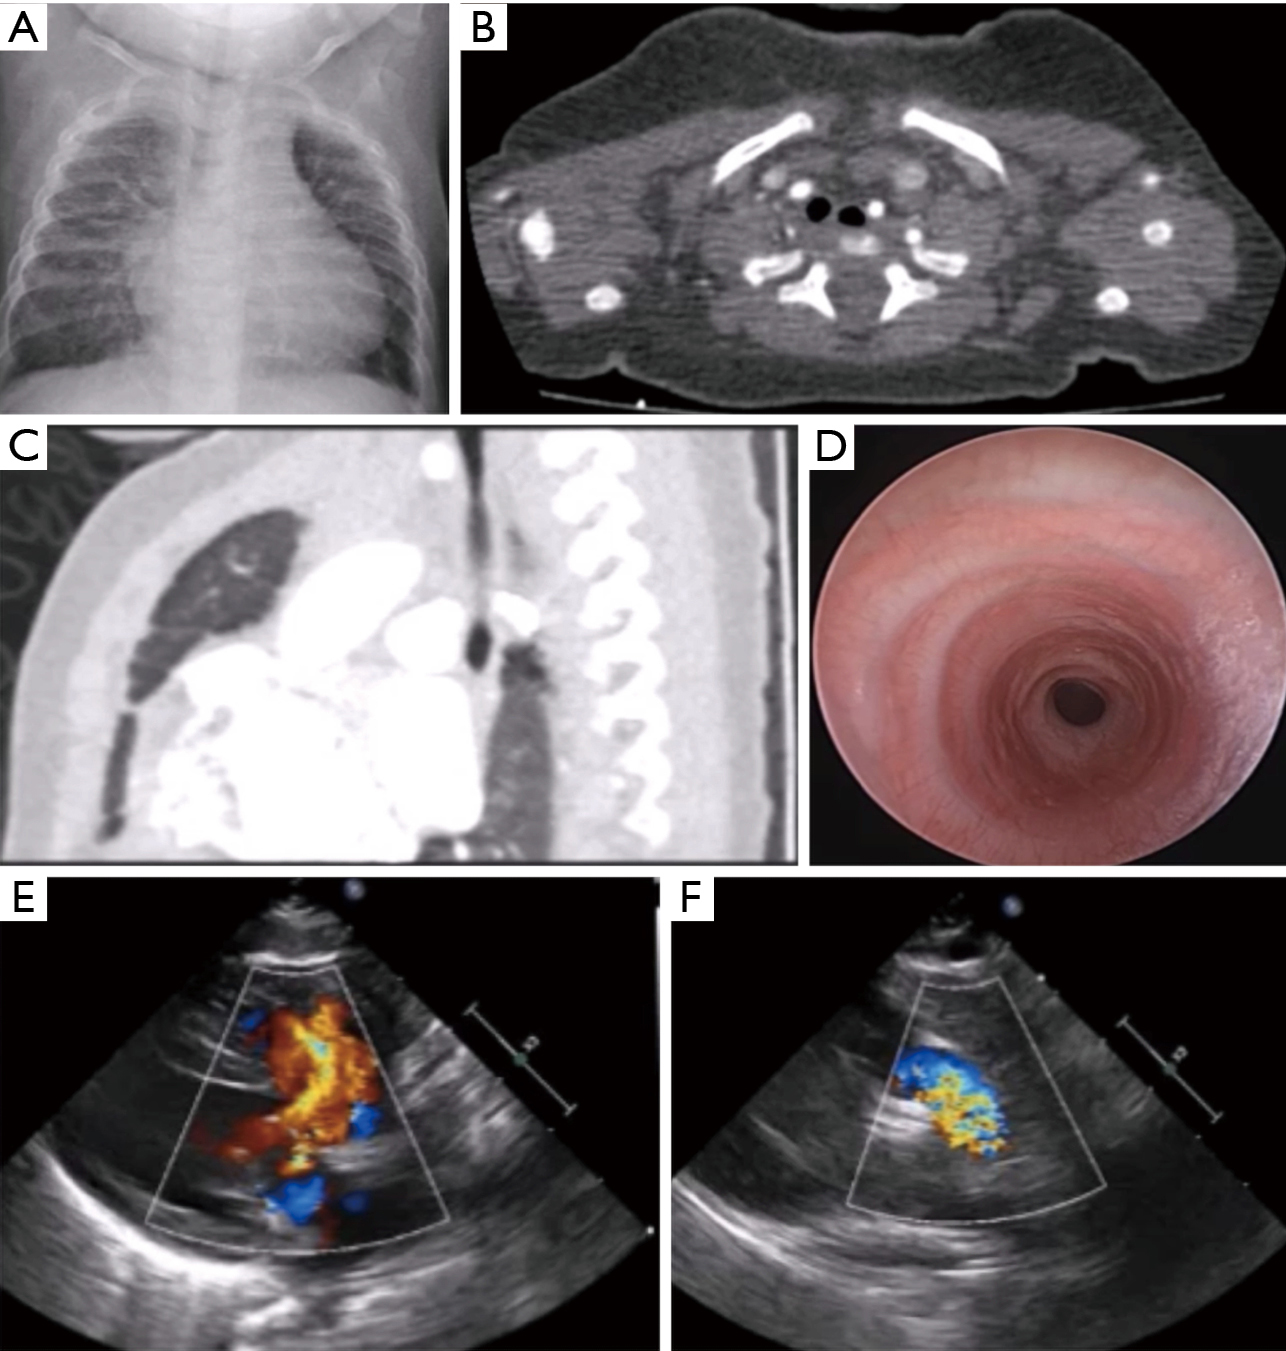

КТ органов грудной клетки. Стеноз правого главного бронха за счет мягкотканного образования в его просвете.

КТ органов грудной клетки. Выраженный стеноз проксимальных отделов трахеи вследствие вторичного распространения опухоли гортани

Первым шагом на пути постановки диагноза является рентгенография и томография трахеи и легких. Рентгенологическими признаками уменьшения просвета дыхательных путей служат форма трахеи в виде песочных часов, неподвижность ее мембранозной стенки, расширение просвета ниже места сужения, ателектаз или эмфизема соответствующего отдела легкого Данные о локализации, протяженности и степени стеноза уточняются посредством контрастных исследований - трахеографии и бронхографии . В выявлении сосудистых аномалий, взывающих стеноз трахеи, велика роль аортографии .

Решающее значение в диагностике стеноза трахеи и бронхов принадлежит эндоскопии дыхательных путей – трахеоскопии, бронхоскопии , в процессе которых есть возможность визуально подтвердить морфологические изменения трахеобронхиальной стенки, уточнить с помощью биопсии этиологию стеноза (рубцовая, опухолевая, туберкулезная). У больных с органическими стенозами трахеи и бронхов исследование ФВД ( спирометрия , пневмотахография ) имеет второстепенное значение (выявляются обструктивные нарушения), однако эти методы широко используются для подтверждения экспираторного стеноза.